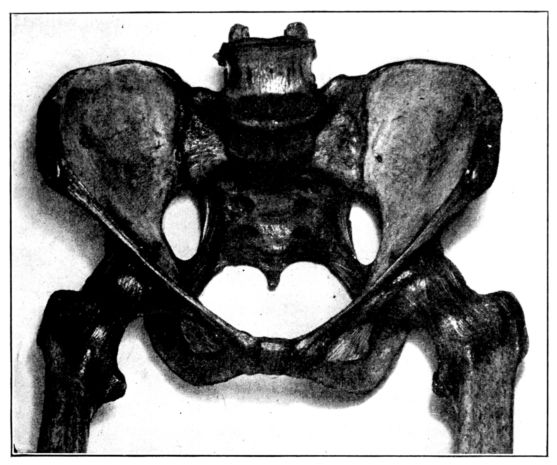

Viewed in its entirety, the pelvis is an irregularly constructed, two-storied, bony cavity, or canal, situated below and supporting the movable parts of the spinal column, and resting upon the femora or thigh bones. (Fig. 1, A. and B.).

A. Normal female Pelvis.

B. Normal male Pelvis.

Fig. 1.—Normal Pelves. Note the broad, shallow, light construction of the female pelvis, A, as compared with the more massive male pelvis, B.

The normal male pelvis is deep, narrow, rough and massive as compared with the female structure (see Fig. 1.), and the angle of the pubic arch, formed by the two pubic bones, is deeper and more acute in the male than in the female skeleton.

The normal female pelvis, on the other hand, is light, broad, shallow, smooth and large, giving evidence of the infinite wisdom and skill that entered into constructing it for the high purpose it was designed to serve.